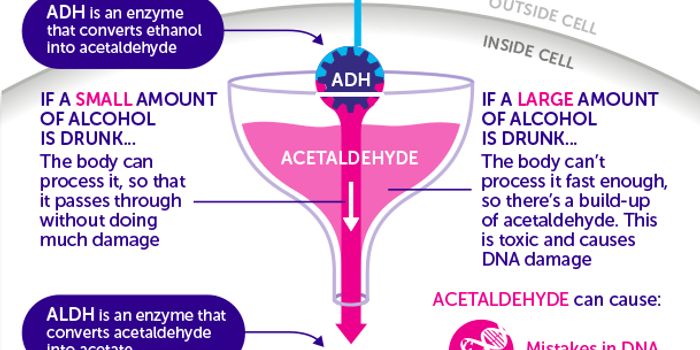

JAN 09, 2018Cancer"This paper provides very strong evidence that an alcohol metabolite causes DNA damage [including] to the all-important ...

JUN 10, 2017CancerMultiple recent studies found adverse links between alcohol consumption and breast cancer. Now a new study may have iden ...